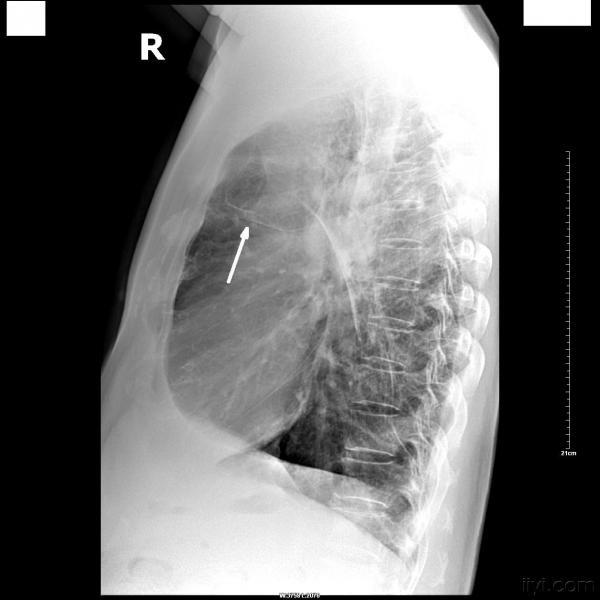

患者,男,59岁,有肺结核病史多年,现咳嗽、气喘,加重一天。

常规胸部正侧(右)位片如下:

发此贴的真正意义是:肺大泡和包裹性气胸的鉴别诊断。

该患者右上肺有胸膜粘连,单纯一张正位片上不排除右下包裹性气胸的诊断,但侧位片未发现粘连胸膜及压缩肺组织边缘,所以右下仍然考虑:巨大肺大泡。